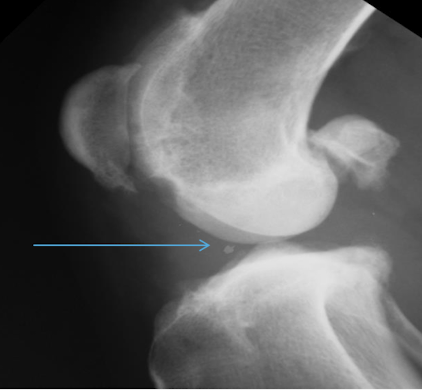

What is the arrow pointing to?

Intra-articular calcified bodies aka joint mouse